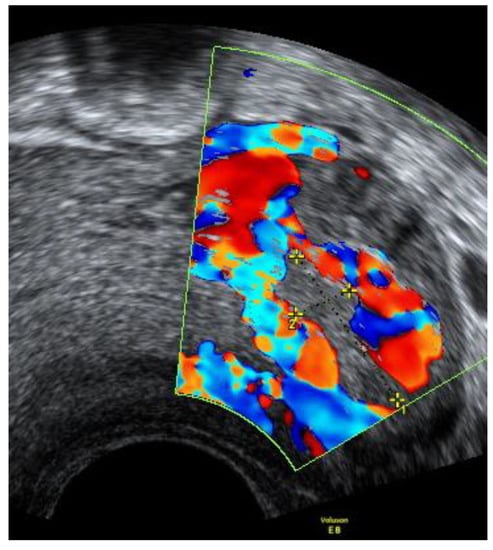

On admission, the patient’s vitals were stable. The patient reported episodic abdominal pain on the left side. Transabdominal ultrasound imaging revealed a hypoechogenic 3.05 × 3.08 cm size mass in the left cornu of the uterus, filled with fluid (without viable embryo), which, by evaluation of the blood flow, could have been related to the uterus. Figure 1.

Figure 1. Left cornu of the uterus visualized by transabdominal ultrasonography on the 13w + 3d.